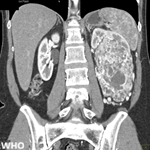

Figure 2: aspects mammographiques

des patientes de l’étude. (a et b): opacité spiculée à centre dense, mal limitée

classée ACR5; (c et d): lésions classées ACR4